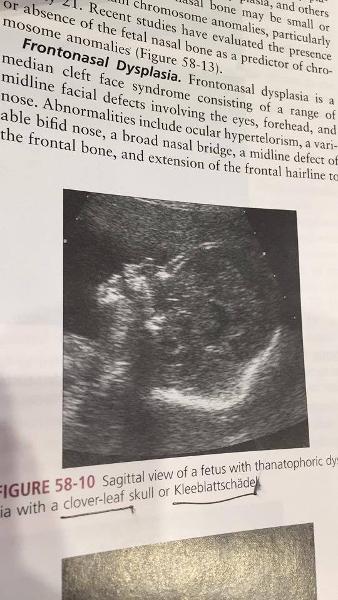

What is Thanatophporic Dysplasia?

severe skeletal disorder characterized by extremely short limbs and folds of extra skin on the arms and legs.

rhizomelia

bowed long bones

narrow thorax

large head

What is the most common form of lethal dwarfism?

Thanatophporic Dysplasia

causes severe micromelia

What is the sonographic appearance of Thanatophporic Dysplasia?

clover leaf skull

narrow chest

short ribs

underdeveloped lungs

enlarged head

large forehead and

prominent, wide-spaced eyes.

Kleeblattshadels

Kleeblattshadels

What is another name for cloverleaf skull?

kleeblattschädel

horseshoe

What are associated anomolies of Thanatophporic Dysplasia?

cloverleaf skull

horseshoe kidneys

ASD

imperforate anus